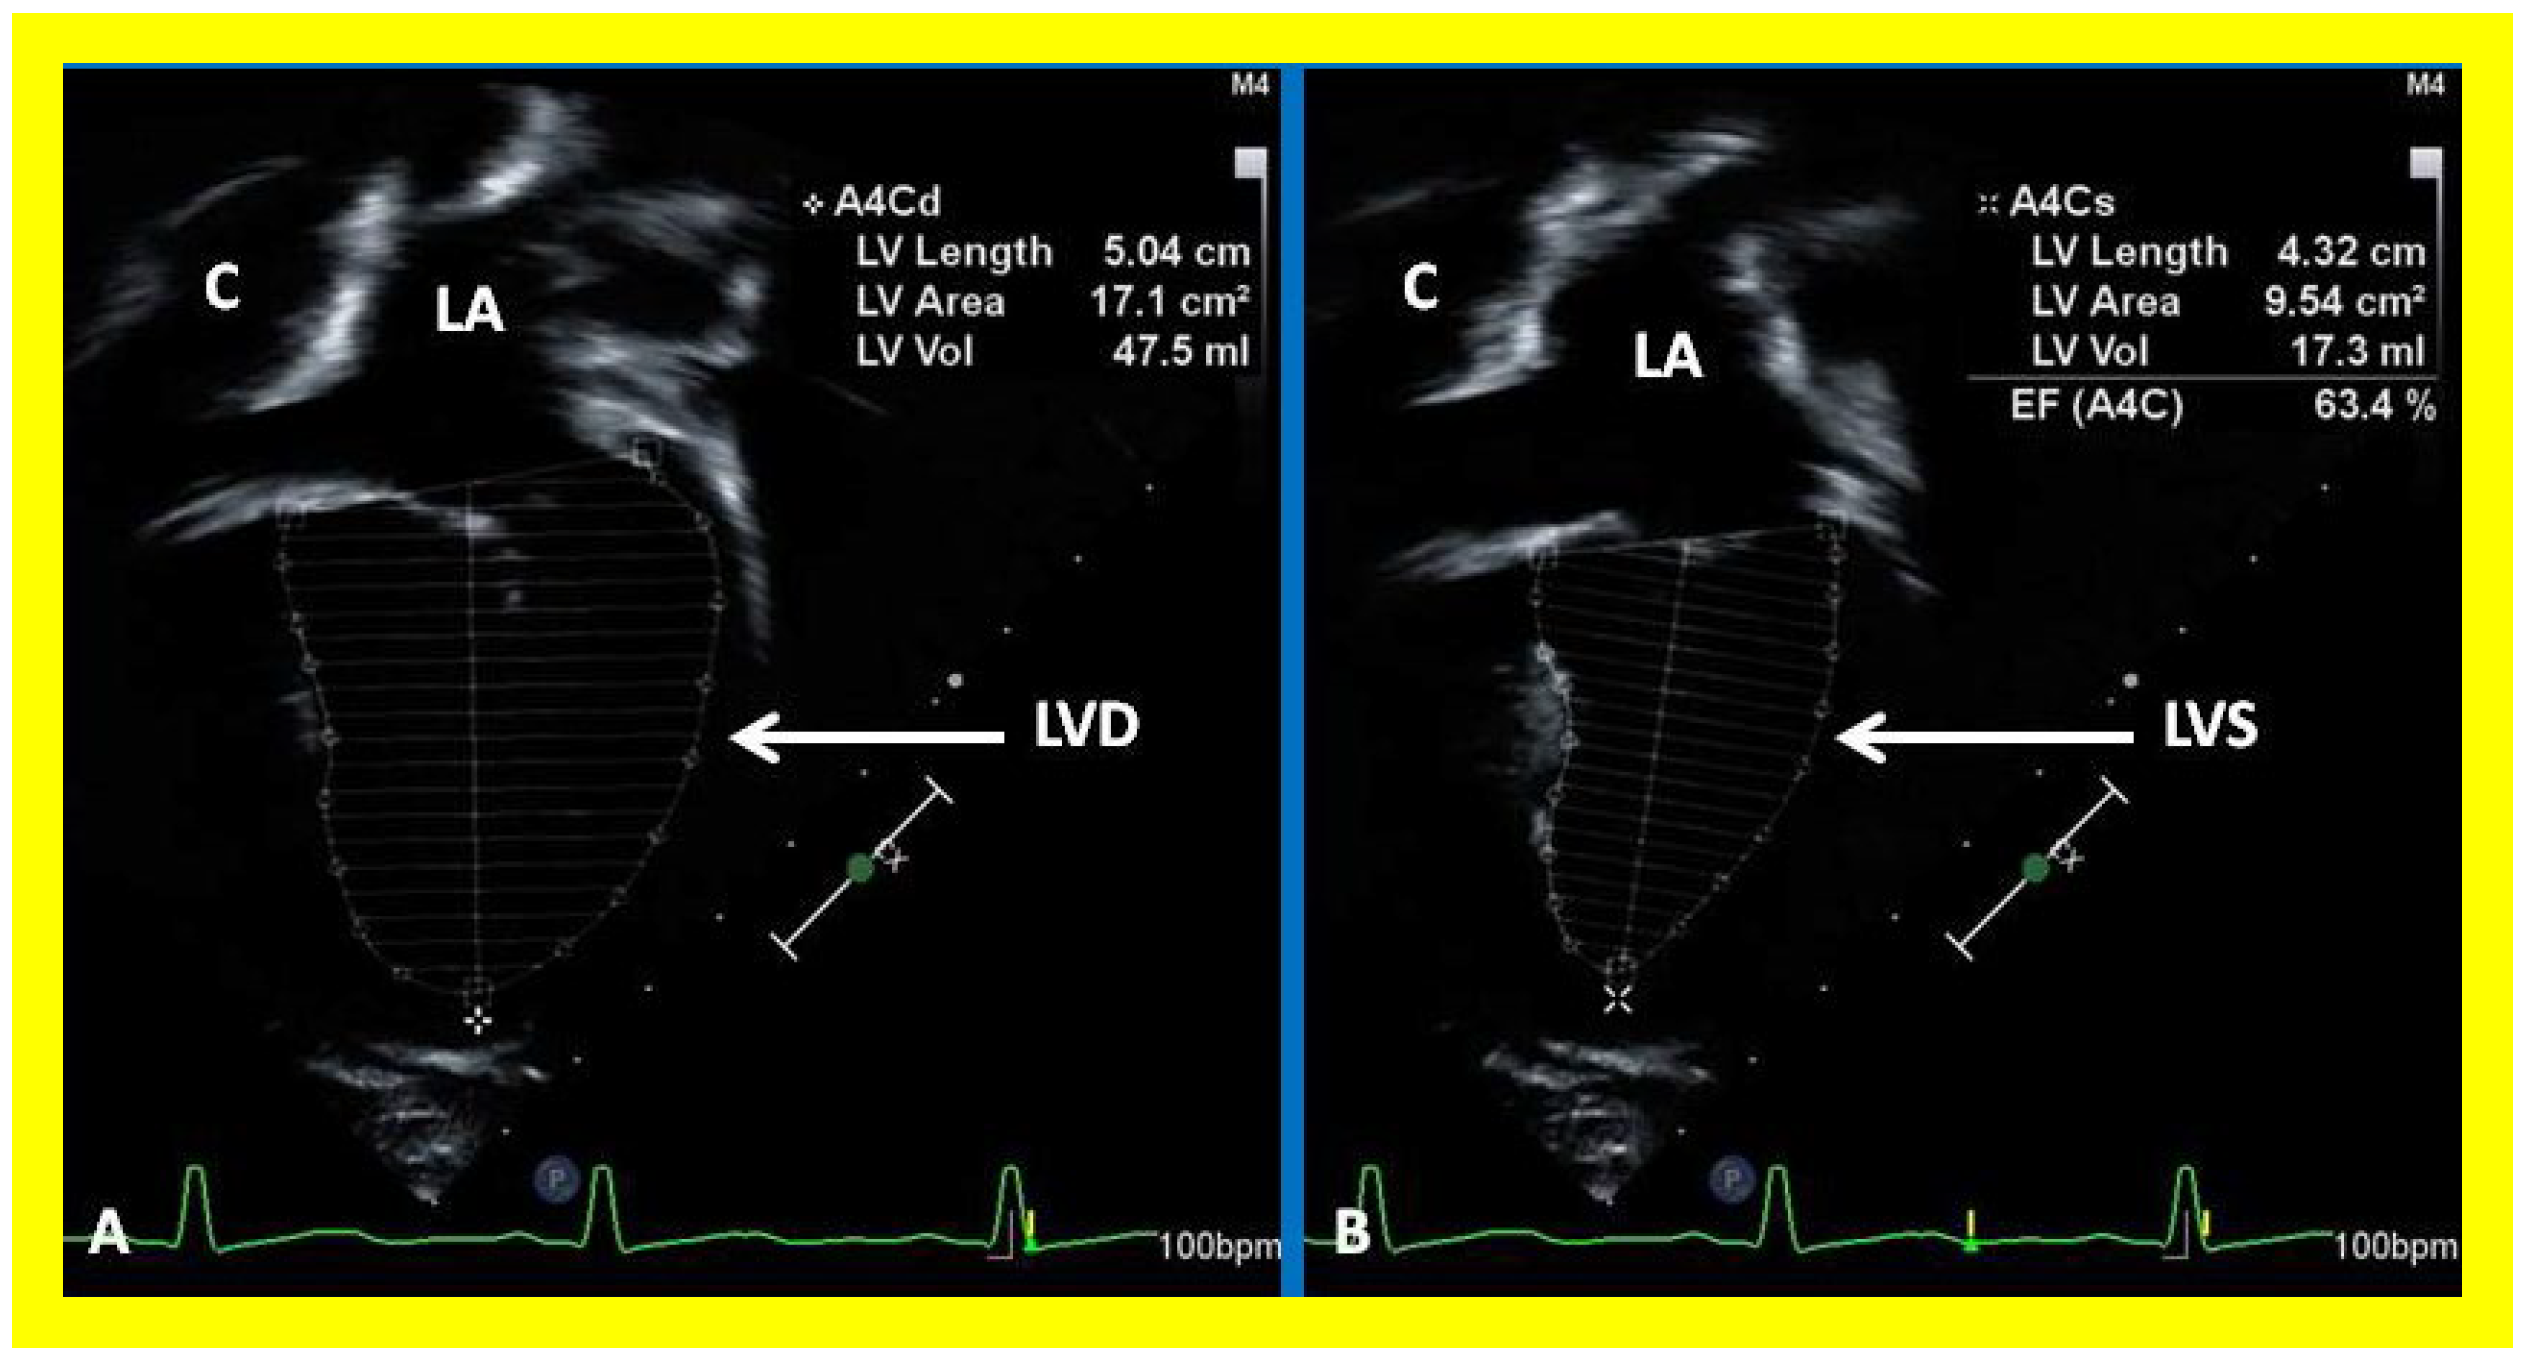

Subsequent to completion of Fontan procedure, periodic clinical follow up along with echo-Doppler studies is generally recommended at 1, 6, and 12 months after the procedure and yearly thereafter [36,37,38]. The LV is usually normal in size with normal LV systolic function (Figure 38) because the pulmonary and systemic circulations are completely separated during the final phase of Fontan. However, some patients may have dilatation of the LV with or without diminished LV systolic function, secondary to prolonged exposure to volume overloading, significant mitral insufficiency, previously undetected myocardial damage due to multiple surgical procedures under cardio–pulmonary bypass, or a combination thereof.

Post-Fontan echocardiographic anatomy is best displayed in apical four chamber views, as demonstrated in Figure 38, Figure 39 and Figure 40. The remnants of the RA and the LA are seen (Figure 38, Figure 39 and Figure 40). The remnants of atrial septum are not usually seen since the atrial septum is completely removed either during bidirectional Glenn or Fontan surgery. Unobstructed pathway allowing emptying of blood flow from the coronary sinus and thebesian veins is usually seen in an apical four chamber view (Figure 40).

Figure 38. Selected video frames showing left ventricle (LV) in diastole (LVD) (A) and in systole (LVS) (B) demonstrating normal ejection fraction (EF) of 63.4%. C, conduit; LA, left atrium.